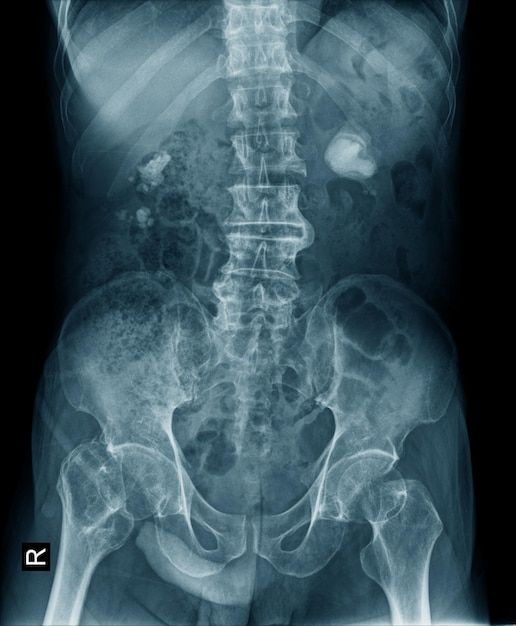

Kidney stones issue

Hello, my name is ugochimereze, and I’m reaching out for support during a very difficult time. Recently, I’ve been dealing with a painful kidney stone that has caused serious health complications. The pain has been overwhelming, and I’ve needed medical treatment that comes with unexpected expenses.